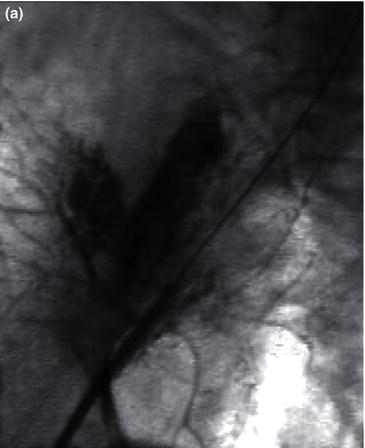

The fluoroscopic C-arm is then positioned over the exposed femoral artery. Retrograde cannulation of the common femoral artery is performed with a beveled needle (18 gauge) until pulsatile blood flow is visualized. A soft-tip angled guide wire is advanced in the vessels under fluoroscopy. The needle is then exchanged for a selected sized dilator and introducer sheath. The dilator is removed and the sheath flushed with heperanized saline. Open cannulation or retrograde percutaneous access can be similarly performed in the contralateral common femoral artery (Fig. 1.10a).

Once the procedure is completed all wires and sheaths are removed under fluoroscopic guidance to ensure no injury is caused to the vessel wall. The arteriotomy is then closed with a 5-0 prolene suture after proximal and distal control is achieved (Fig. 1.10b).

Fig. 1.10 (a) Open retrograde cannulation of the right common femoral artery and percutaneous retrograde cannulation of the left common femoral artery. (b) Closure of the arteriotomy after removal of the guide wire and introduction sheath.